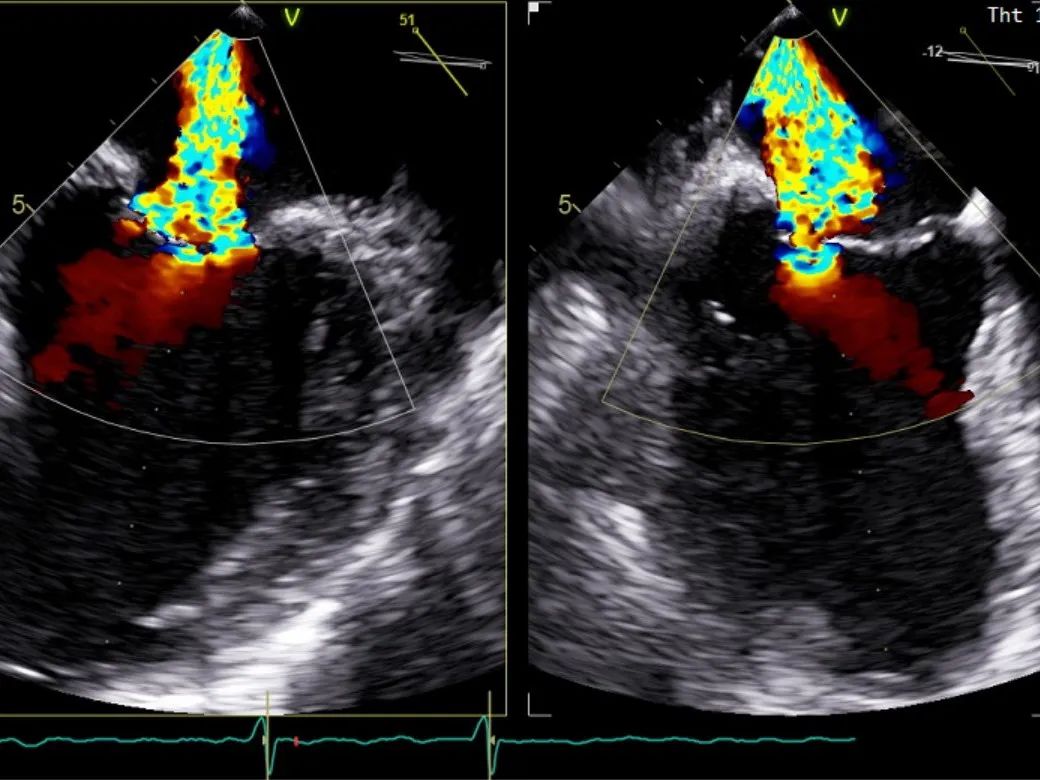

二尖瓣在收缩期变成双孔状,反流有效减小

周浩主任继续在食道超声影像引导下进行高难度操作,在第一个二尖瓣夹内侧再置入第二枚二尖瓣夹。

再次反复测试第二枚二尖瓣钳夹的稳定性,超声复查提示二尖瓣反流明显改善,平均跨瓣压差4 mmHg